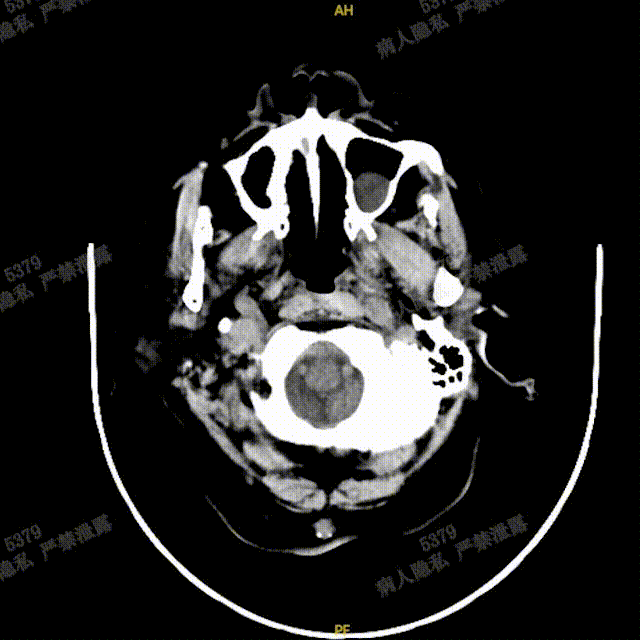

工作角度、侧位造影CT复查结果观察,载瘤动脉通畅、支架贴壁良好、动脉瘤内造影剂滞留,颅内未见明显异常。

完全释放FRED 5514血流导向密网支架,正、侧位造影及术后CT复查结果观察,载瘤动脉通畅、支架贴壁良好、动脉瘤内造影剂滞留、颅内未见明显异常。

正、侧位造影及术后CT复查结果观察,载瘤动脉通畅、支架贴壁良好、动脉瘤内造影剂滞留、颅内未见明显异常。